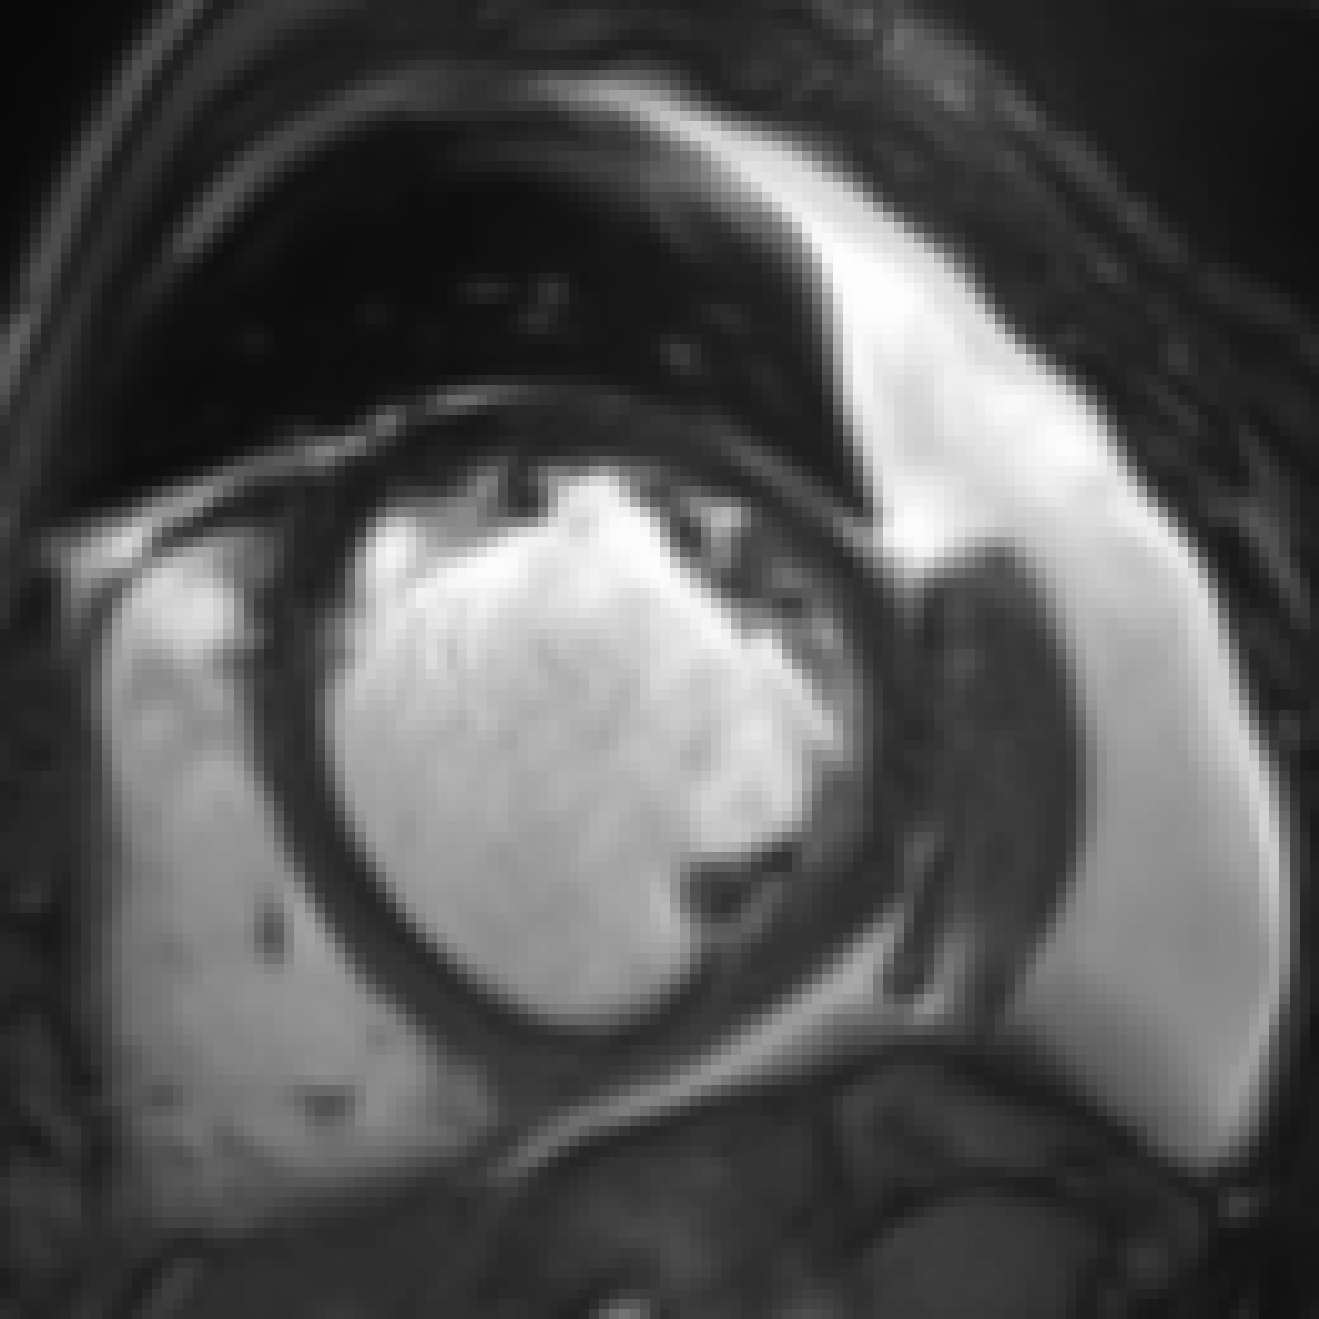

Figure 5: Qualitative evaluation of image synthesis performance of proposed method on cardiac cine MRI (ACDC dataset). Slice spacing was improved from 101010 to 1.43 mmtimes1.43millimeter1.43\text{\,}\mathrm{mm} by synthesizing six intermediate slices (second to penultimate columns) using latent space encodings of the two neighboring slices (first and last column). α𝛼\alpha denotes the mixing coefficient as specified in Equation 1.

Slice Synthesis: Qualitative evaluation of synthesis performance of the proposed method conveys that synthesized slices, i.e. those that are generated using a convex combination of the neighboring slice encodings, show an anatomically and semantically meaningful transition between the two neighboring slices. Moreover, despite large anatomical variations between the neighboring slices for the right ventricle, left ventricle and trabecular structures of the left ventricle, the proposed method can generate slices that depict an anatomically smooth transition between the neighboring slices. Figure 5 illustrates three example evaluations for basal, mid-ventricular and apical MRI slices, respectively, where upsampling factor K𝐾K was set to 777 and 𝒜𝒜\mathcal{A}, the set of mixing coefficients was equal to {1/7,2/7,3/7,4/7,5/7,6/7}172737475767\{\nicefrac{{1}}{{7}},\nicefrac{{2}}{{7}},\nicefrac{{3}}{{7}},\nicefrac{{4}}{{7}},\nicefrac{{5}}{{7}},\nicefrac{{6}}{{7}}\}. Furthermore, quantitative evaluation of synthesis performance assessed on downsampled cardiac cine MRI scans listed in Table I reveals that synthesis performance is lower than reconstruction performance.